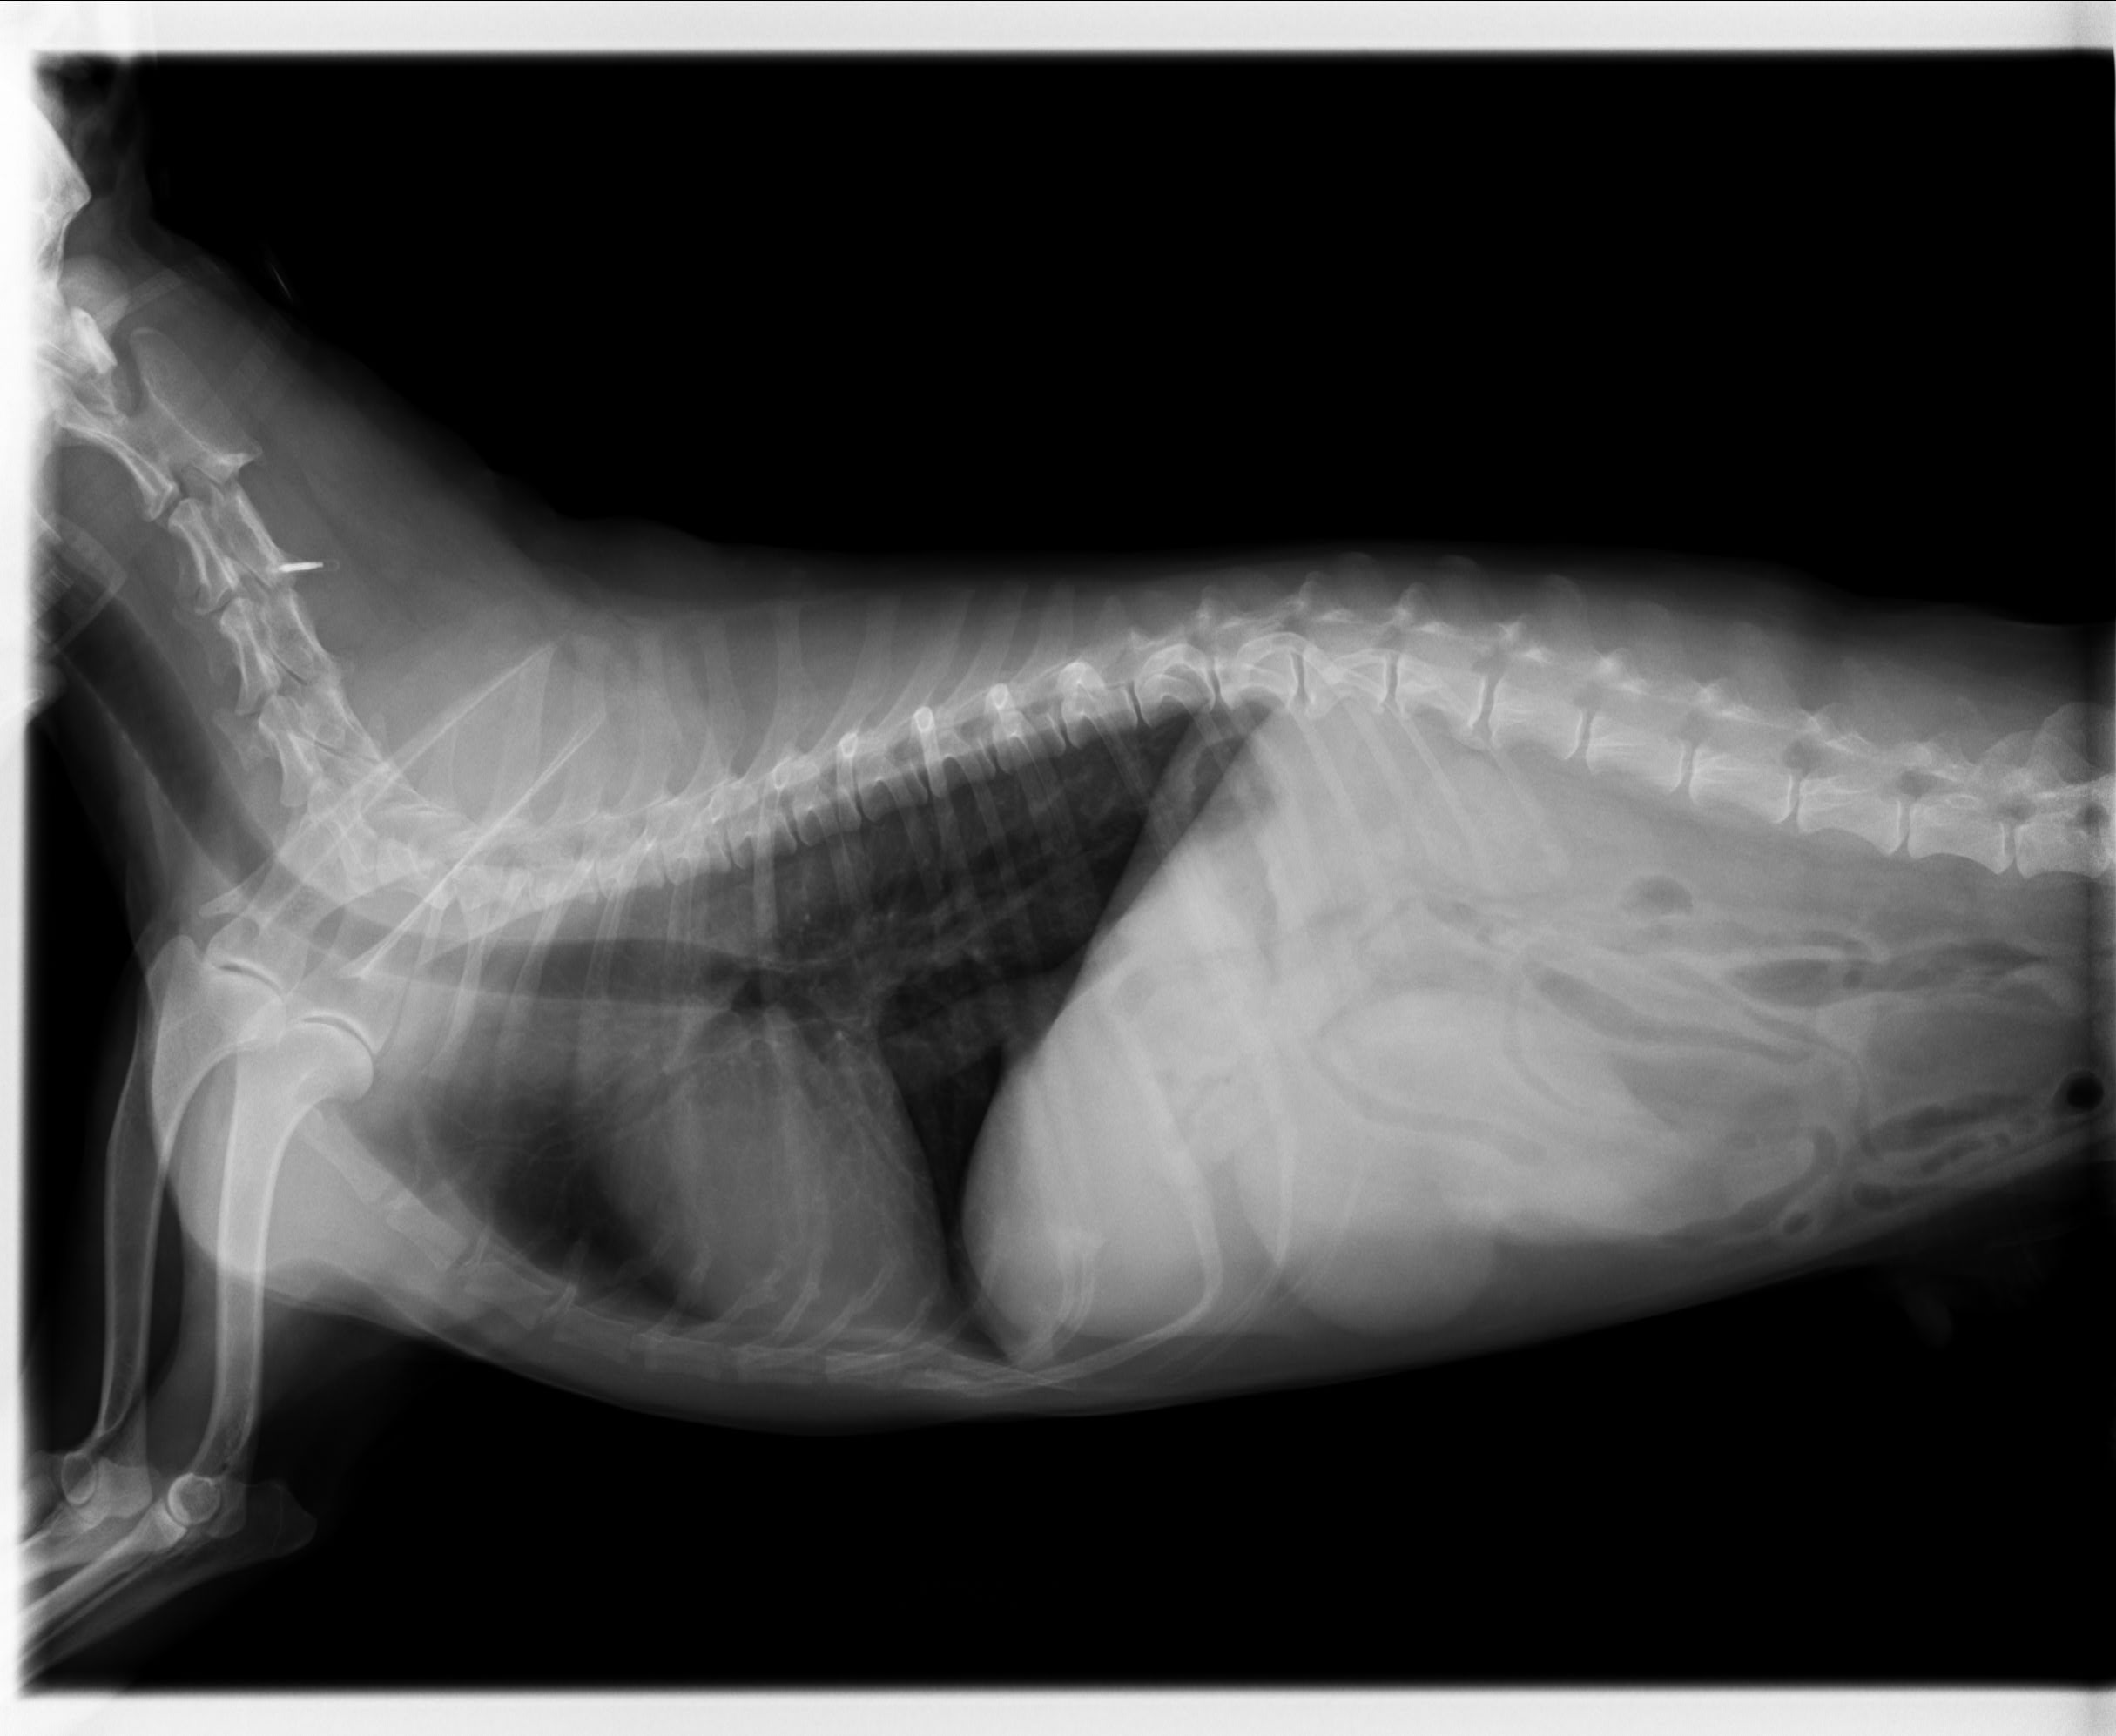

レントゲン検査、超音波検査にて脾臓に大きなしこりが見つかりました。

(今回の胃腸障害・発熱は、脾臓のしこりが小破裂をしたところにお腹の中の脂肪が癒着したため炎症が起きて腹膜炎に繋がったためと推測されました)